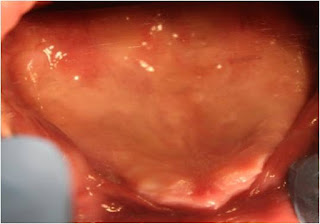

FLAPLESS 11 BASAL IMPLANTS PLACED IN UPPER JAW